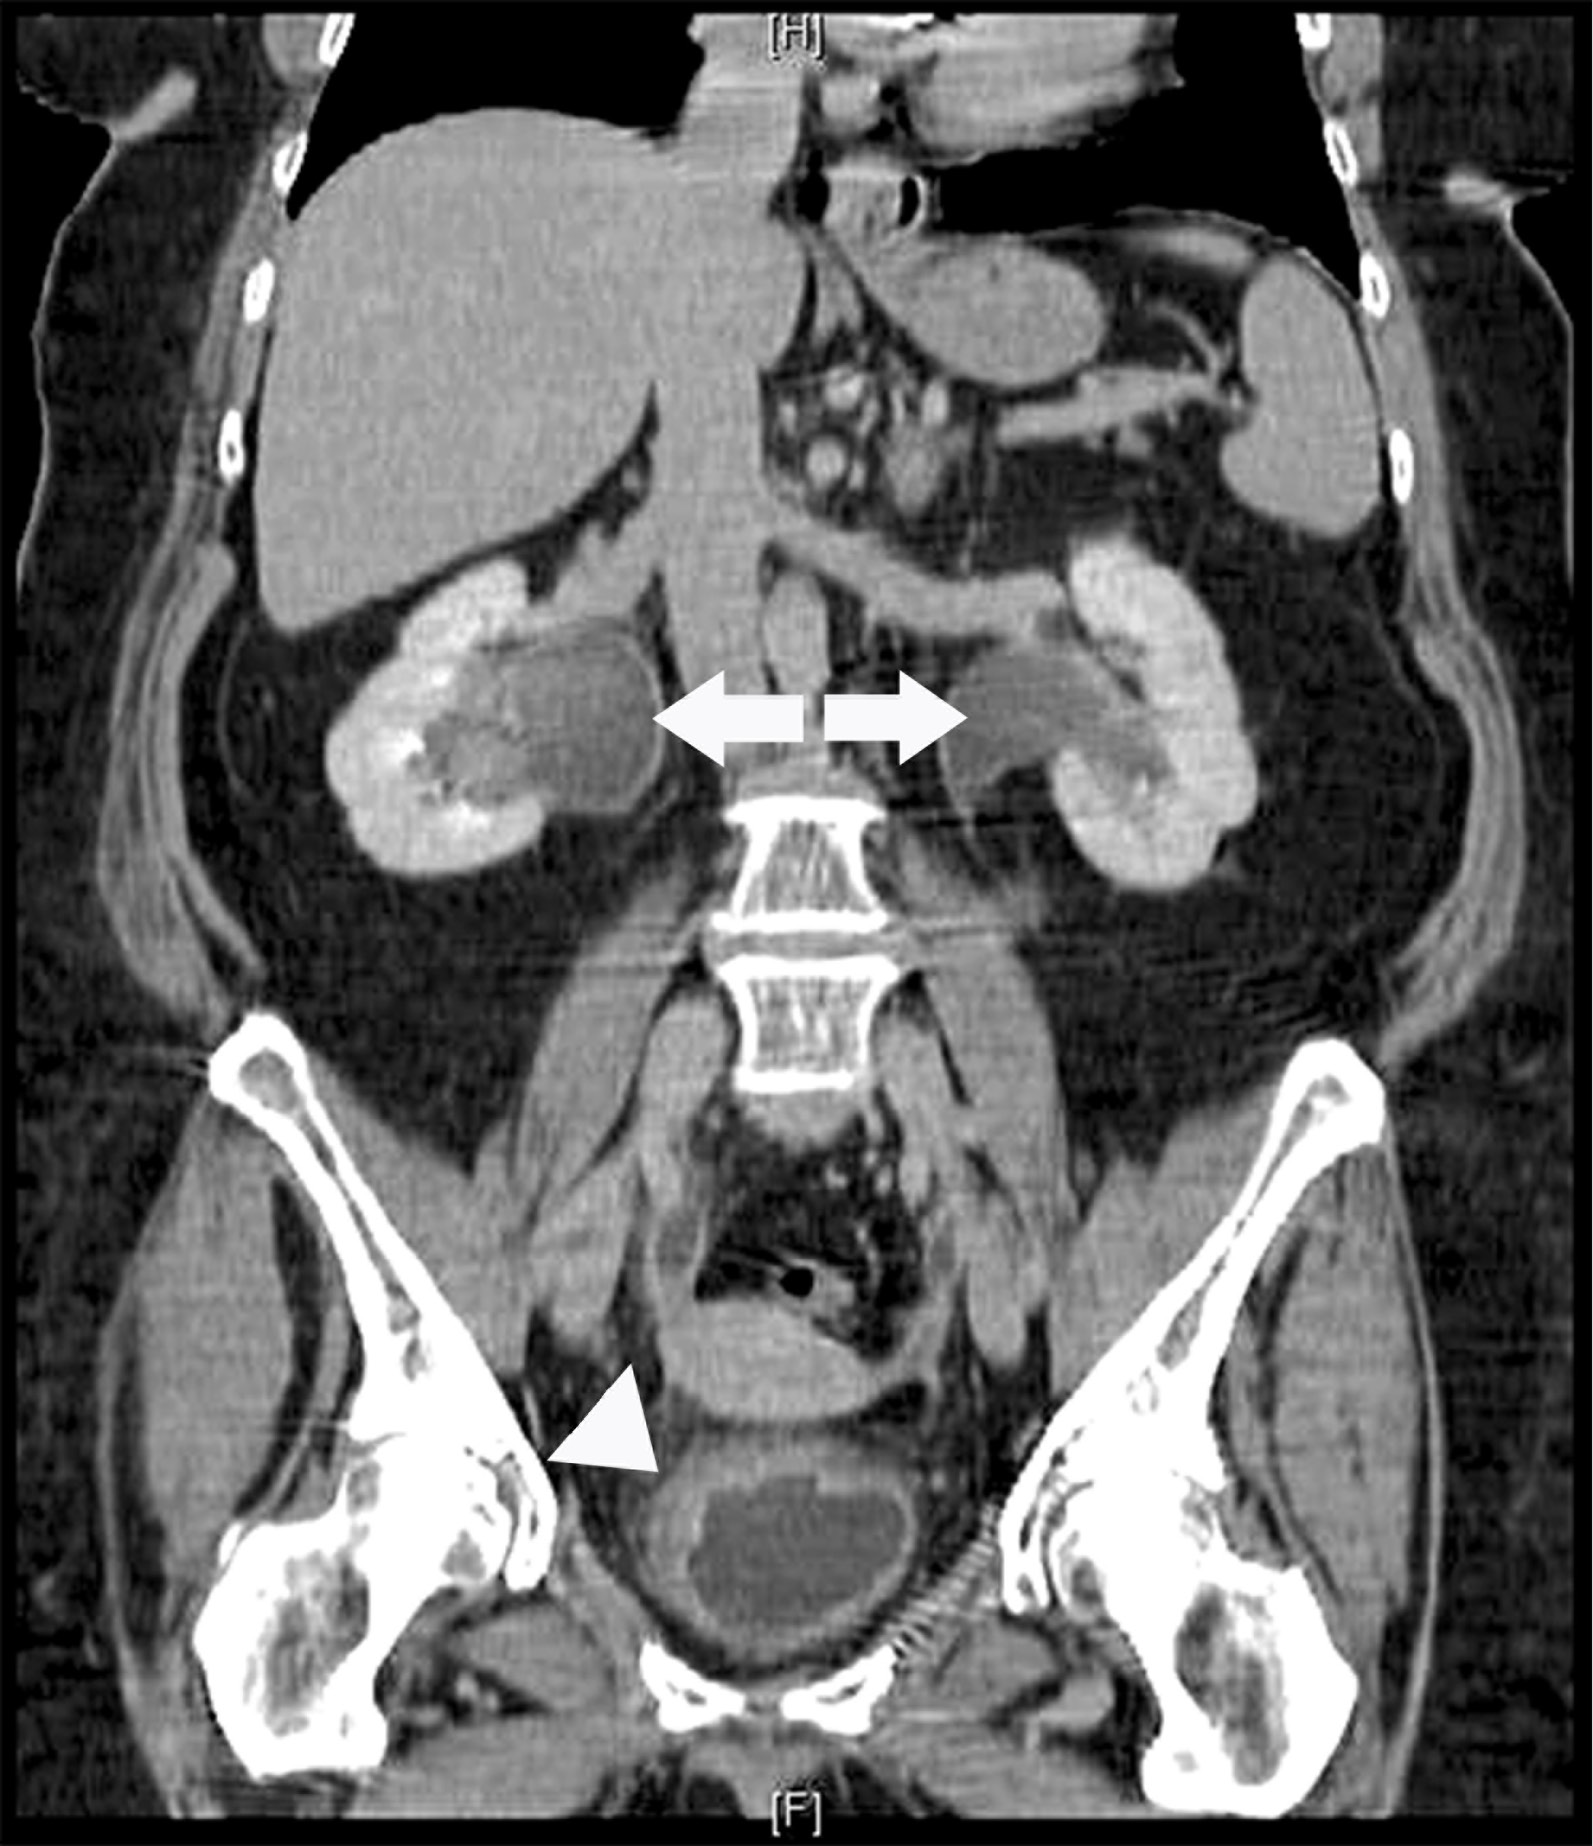

Gross hematuria, irritative lower urinary tract symptoms, and bilateral hydroureteronephrosis: A concerning presentation of an ultimately benign case of concurrent nephrogenic adenoma and eosinophilic cystitis